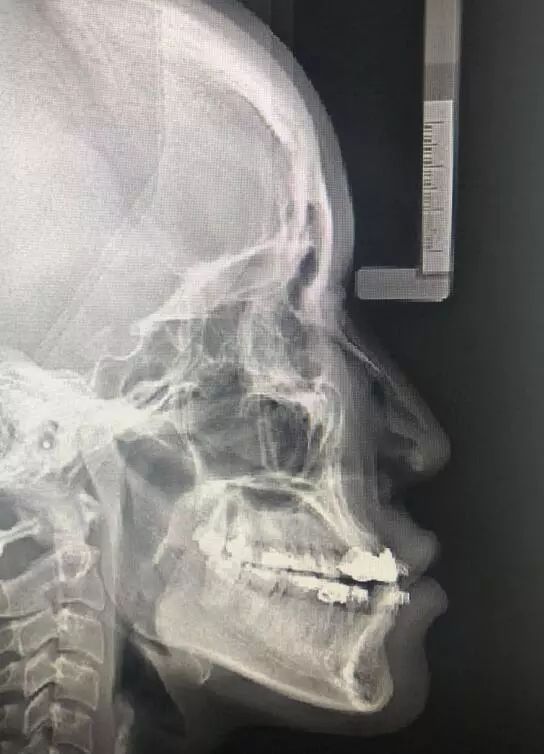

地包天拍片

地包天拍片,

从一台双鄂手术案例谈起,地包天性长脸的face off(变脸